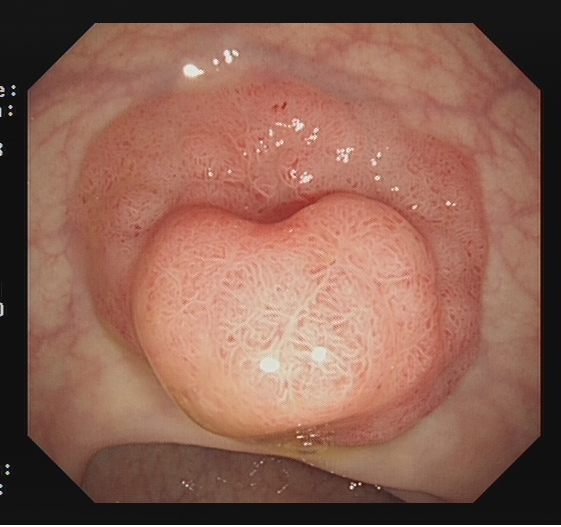

适用于不同大小隆起型病变Ⅰp型、Ⅰsp 型以及小型(<2 cm)Ⅰs型(具体分型标准可参照内镜发现消化道早癌,分型太多不知道怎么判断?这篇文章讲清楚了)病变的切除。小型Ⅰp型病变,圈套切除相对简单,可采用冷或热圈套切除,切除时应在保证完整切除病变同时,保留一定长度的蒂部或与肠壁保持一定距离,收紧圈套后,应抖动圈套器,观察有无周围正常肠黏膜一并套入,防止损伤肠壁。

图2 小型Ⅰsp 型病变热圈套切除示意图